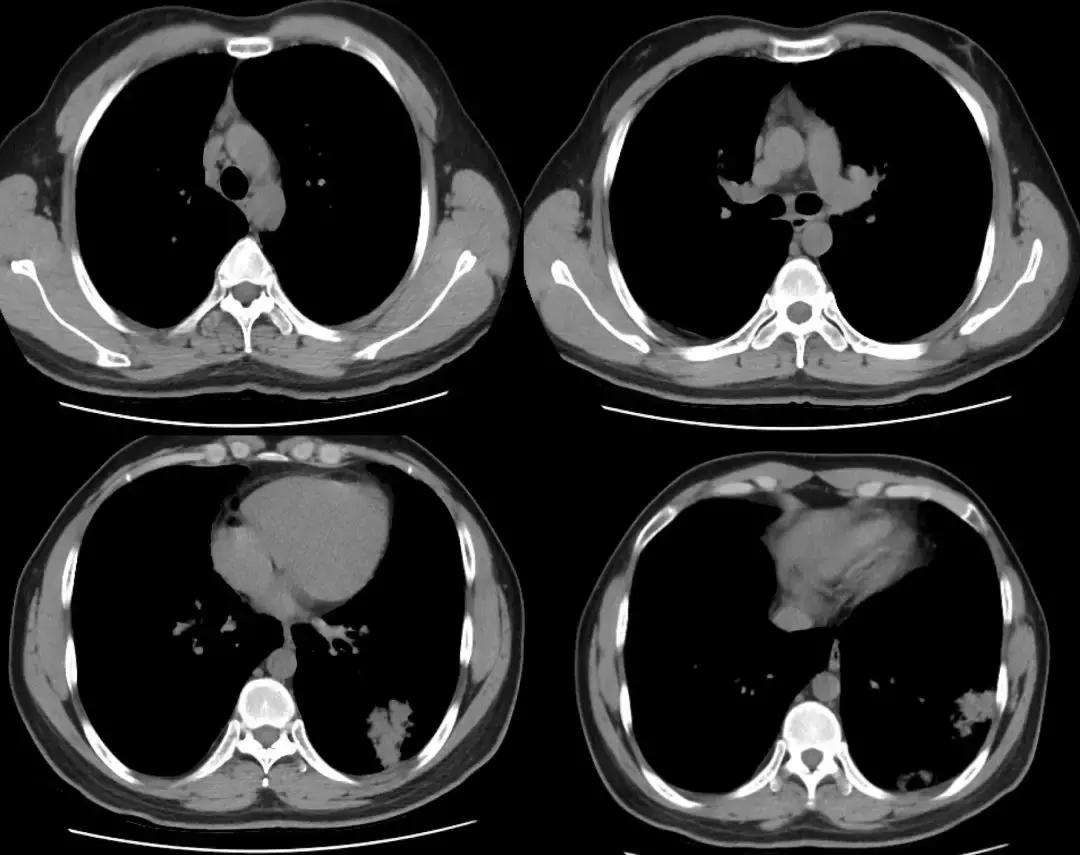

复查胸部CT(2018-1-29),对比原片如下图:

1、两肺野弥漫病变较前未见明显变化,两肺上叶陈旧病变同前

2、左肺下叶片状密度增高影较前范围增大,密度增高

3、纵膈内多发淋巴结,大者位于气管隆突下,短径约1.1cm,较前未见明显变化;余基本同前。